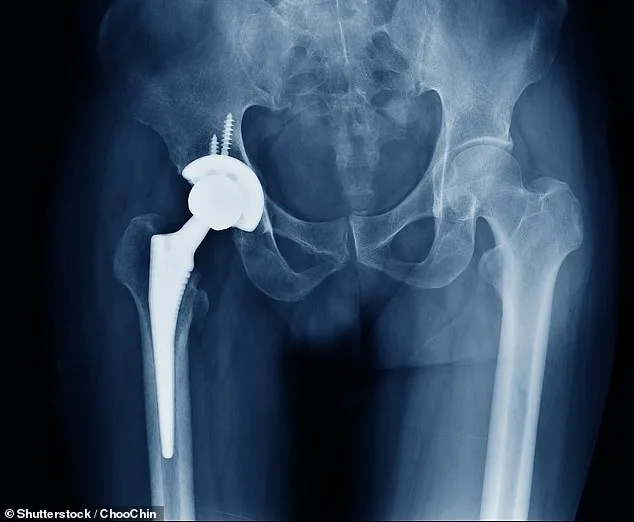

Bone cement plays a crucial role in joint replacement surgery, securing implants and enabling faster recovery. It is used in over 80% of knee replacements and nearly 60% of hip procedures, translating to 15,000 operations monthly. The disruption has raised alarms among patient advocacy groups, with Arthritis UK describing the situation as a 'crushing blow.' Dr. Alex Dickinson, a prosthetics engineering professor at the University of Southampton, explained that while alternatives exist, they require extensive development and clinical validation to ensure patient safety. 'Implant engineering is a cautious process,' he said. 'Any new technology carries risks, and thorough testing is essential to minimise harm.'